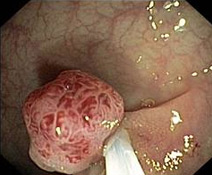

Eines der wichtigsten therapeutischen Verfahren der modernen

gastroenterologischen Medizin stellt die Abtragung von Polypen

(Polypektomie) dar.

Aus zunächst gutartigen Polypen im Darm (seltener auch in

anderen Bereichen des Magen-Darm-Trakts) kann sich ein

Darmkrebs entwickeln.

Diese Entwicklung wird durch die Abtragung der Polypen

verhindert. Dabei wird in besonders schonendem Verfahren der

Polyp mit einer Elektroschlinge abgetragen. Hierbei handelt es

sich also nicht nur um eine ‚Früherkennung', sondern um

‚Vorsorge' im eigentlichen Sinn. Der Darmkrebs wird nicht nur

früh erkannt, sondern verhindert.